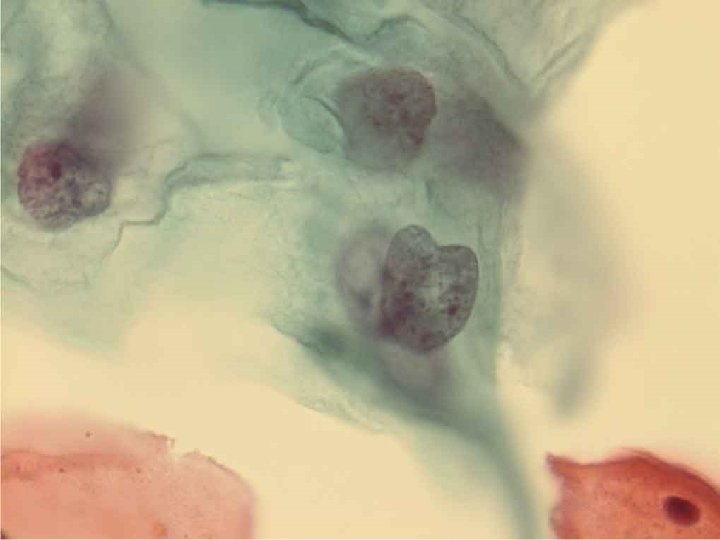

Молекулярные исследования при заболеваниях шейки матки Диагностика и прогноз развития интраэпителиальной неоплазии • p 16, p 53 • Метилирование ДНК Гены DAPK, HIN 1, MGMT, RAR-β, RASSF 1 A, SHP 1 – увеличение с увеличением степени дисплазии MGMT, RAR-β, Twist – увеличение частоты метилирования при HSIL-Cr

Результаты тестов: р16 и ВПЧ при проблемах интерпретации (ASC-US/ASCH) • В 11 из 17 наблюдений с ASC-US/ ASC-H отмечена экспрессия р16, причем в 10 из них гистологически выявлены HSIL+